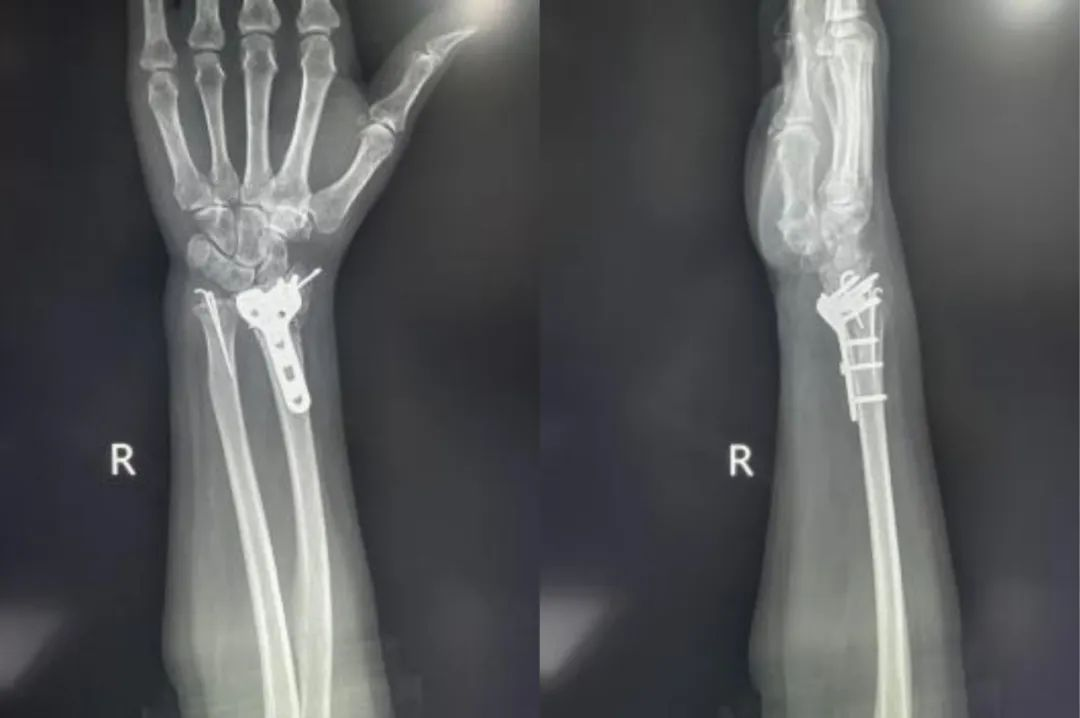

Случай ①